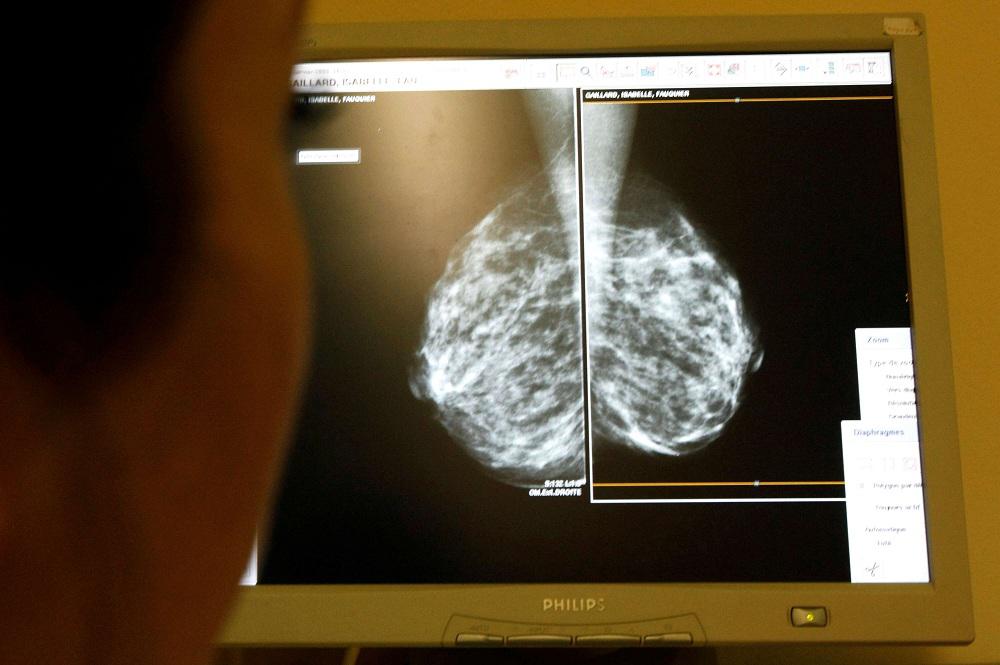

باريس - تكثر خلال شهر تشرين الأول/أكتوبر من كل عام الحملات التي تدعو النساء للخضوع لفحوص الكشف عن سرطان الثدي... غير أن الجسم الطبي يشهد جدلا بين جهات تؤيد تعميم التصوير الشعاعي على أوسع نطاق، وأخرى تحذر من خطر تلقي النساء علاجات غير ضرورية.

وتتماشى هذه التصريحات مع توجيهات السلطات الصحية في البلدان المتقدمة الرئيسية، إذ يعتمد الكثير منها سياسة تعميم الفحوص، مثل فرنسا حيث تتم دعوة النساء اللواتي تتراوح أعمارهن بين 50 و 74 عاما إلى الخضوع لتصوير الثدي بالأشعة كل عامين، ويلبي نصفهنّ هذه الدعوة.

ويتركز النقاش على مخاطر "الإفراط في التشخيص". في الواقع، يمكن للتصوير الشعاعي للثدي أن يكشف ورماً لن يتطور أبداً إلى سرطان الثدي. لكن من المستحيل معرفة ذلك مسبقا وسيخضع بعض المرضى، كإجراء وقائي، لعلاجات غير ضرورية في الواقع يمكن أن تصل إلى حد إزالة الثدي.